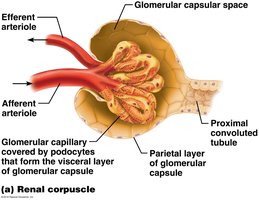

Renal Corpuscle: Includes the glomerulus (fenestrated capillary bed) and Bowman’s capsule (with podocytes forming filtration slits).

Renal Tubules: Proximal convoluted tubule (PCT), loop of Henle, distal convoluted tubule (DCT), and collecting duct.

The filtration membrane consists of three layers: fenestrated endothelium, basement membrane, and podocyte filtration slits. It allows passage of water, ions, glucose, amino acids, and small proteins, but restricts blood cells and large proteins.